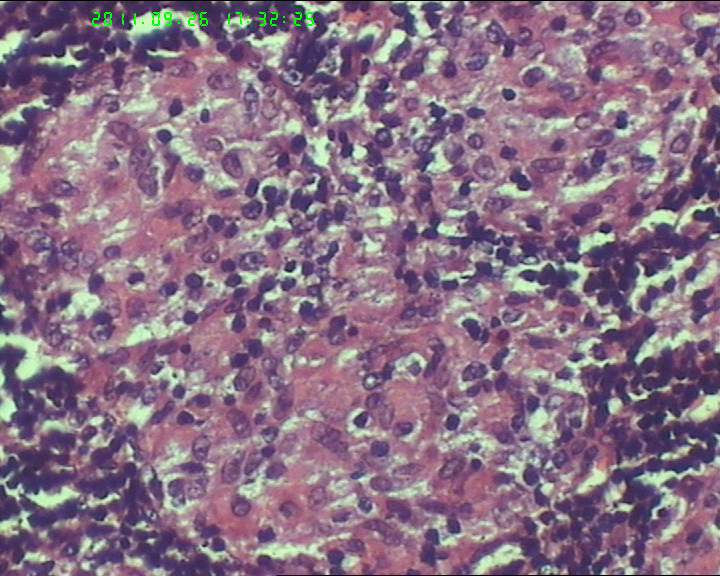

21岁女性左侧颌下淋巴结,该诊断什么?

灰白不整形肿物一个,大小3.5*2.5*2cm,包膜完整。

21岁女性左侧颌下淋巴结,该诊断什么?图1

慢性肉芽肿性炎症,形态学倾向结节病,但是作为病理工作者对于这样的病例,再结合咋们国情,还是建议临床除外增殖性结核后再考虑结节病。

肉芽肿性炎症,倾向结节病。